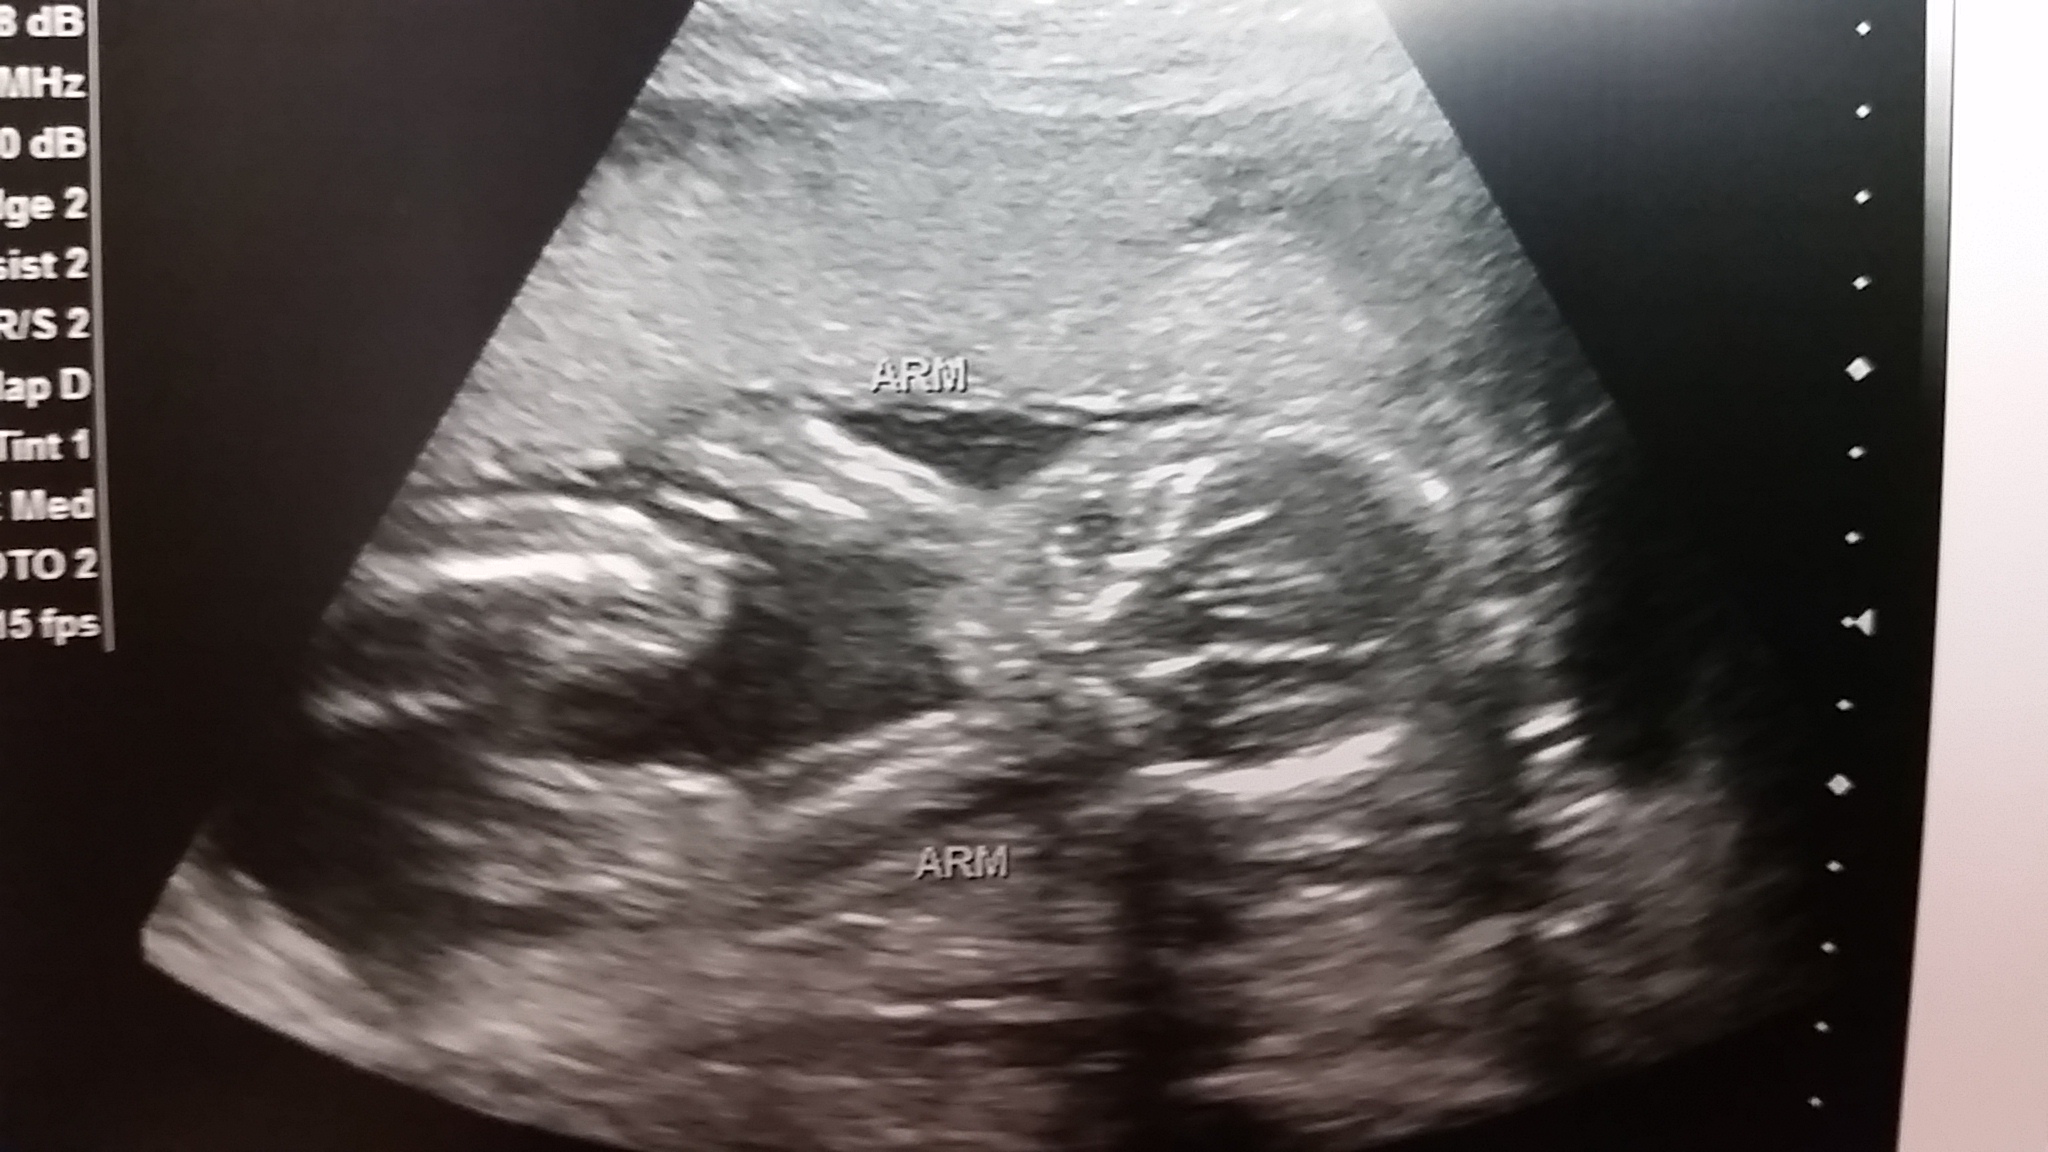

Turtle!!!

Just kidding, but DH did make that joke when the tech said "it looks like you're having a..." DH: "TURTLE!"

We're actually having a boy though. Doc audibly said "whoa" in reference to our large 18oz child! HB was 139, which I hear is pretty standard.

We actually almost thought we wouldn't find out the sex because he would uncross his legs. He went spread eagle right at the end though. No missing the man-dangle.

He was very active and kept waving at us. It was so much fun watching him on the big screen for an hour straight!

Thanks everyone! It was nice to have them point out two arms, two legs, hands, feet brain...

I feel like it got very REAL in that office!